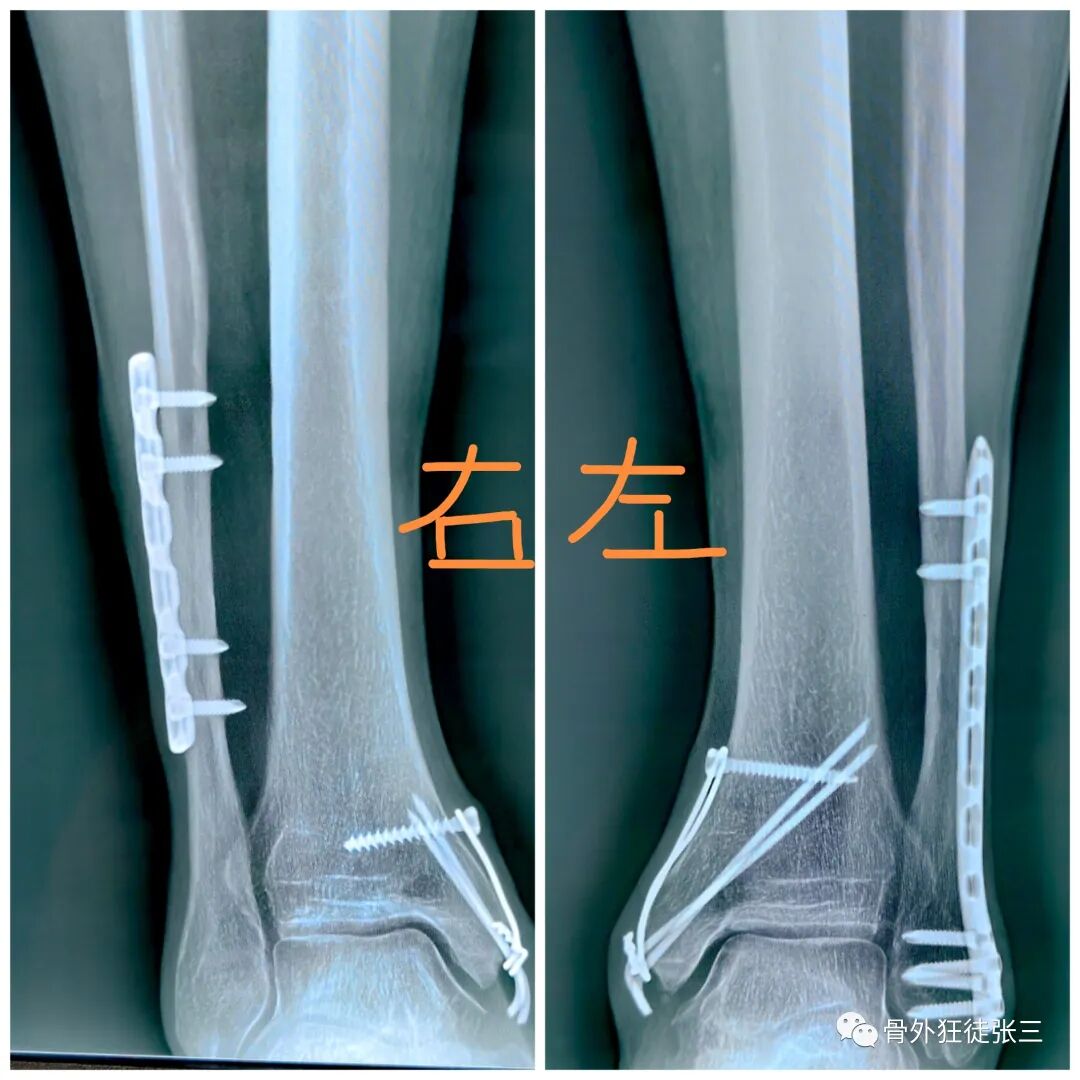

病例29,双内踝骨折,克氏针张力带

病例47,开放性踝关节骨折,二期内踝克氏针内固定